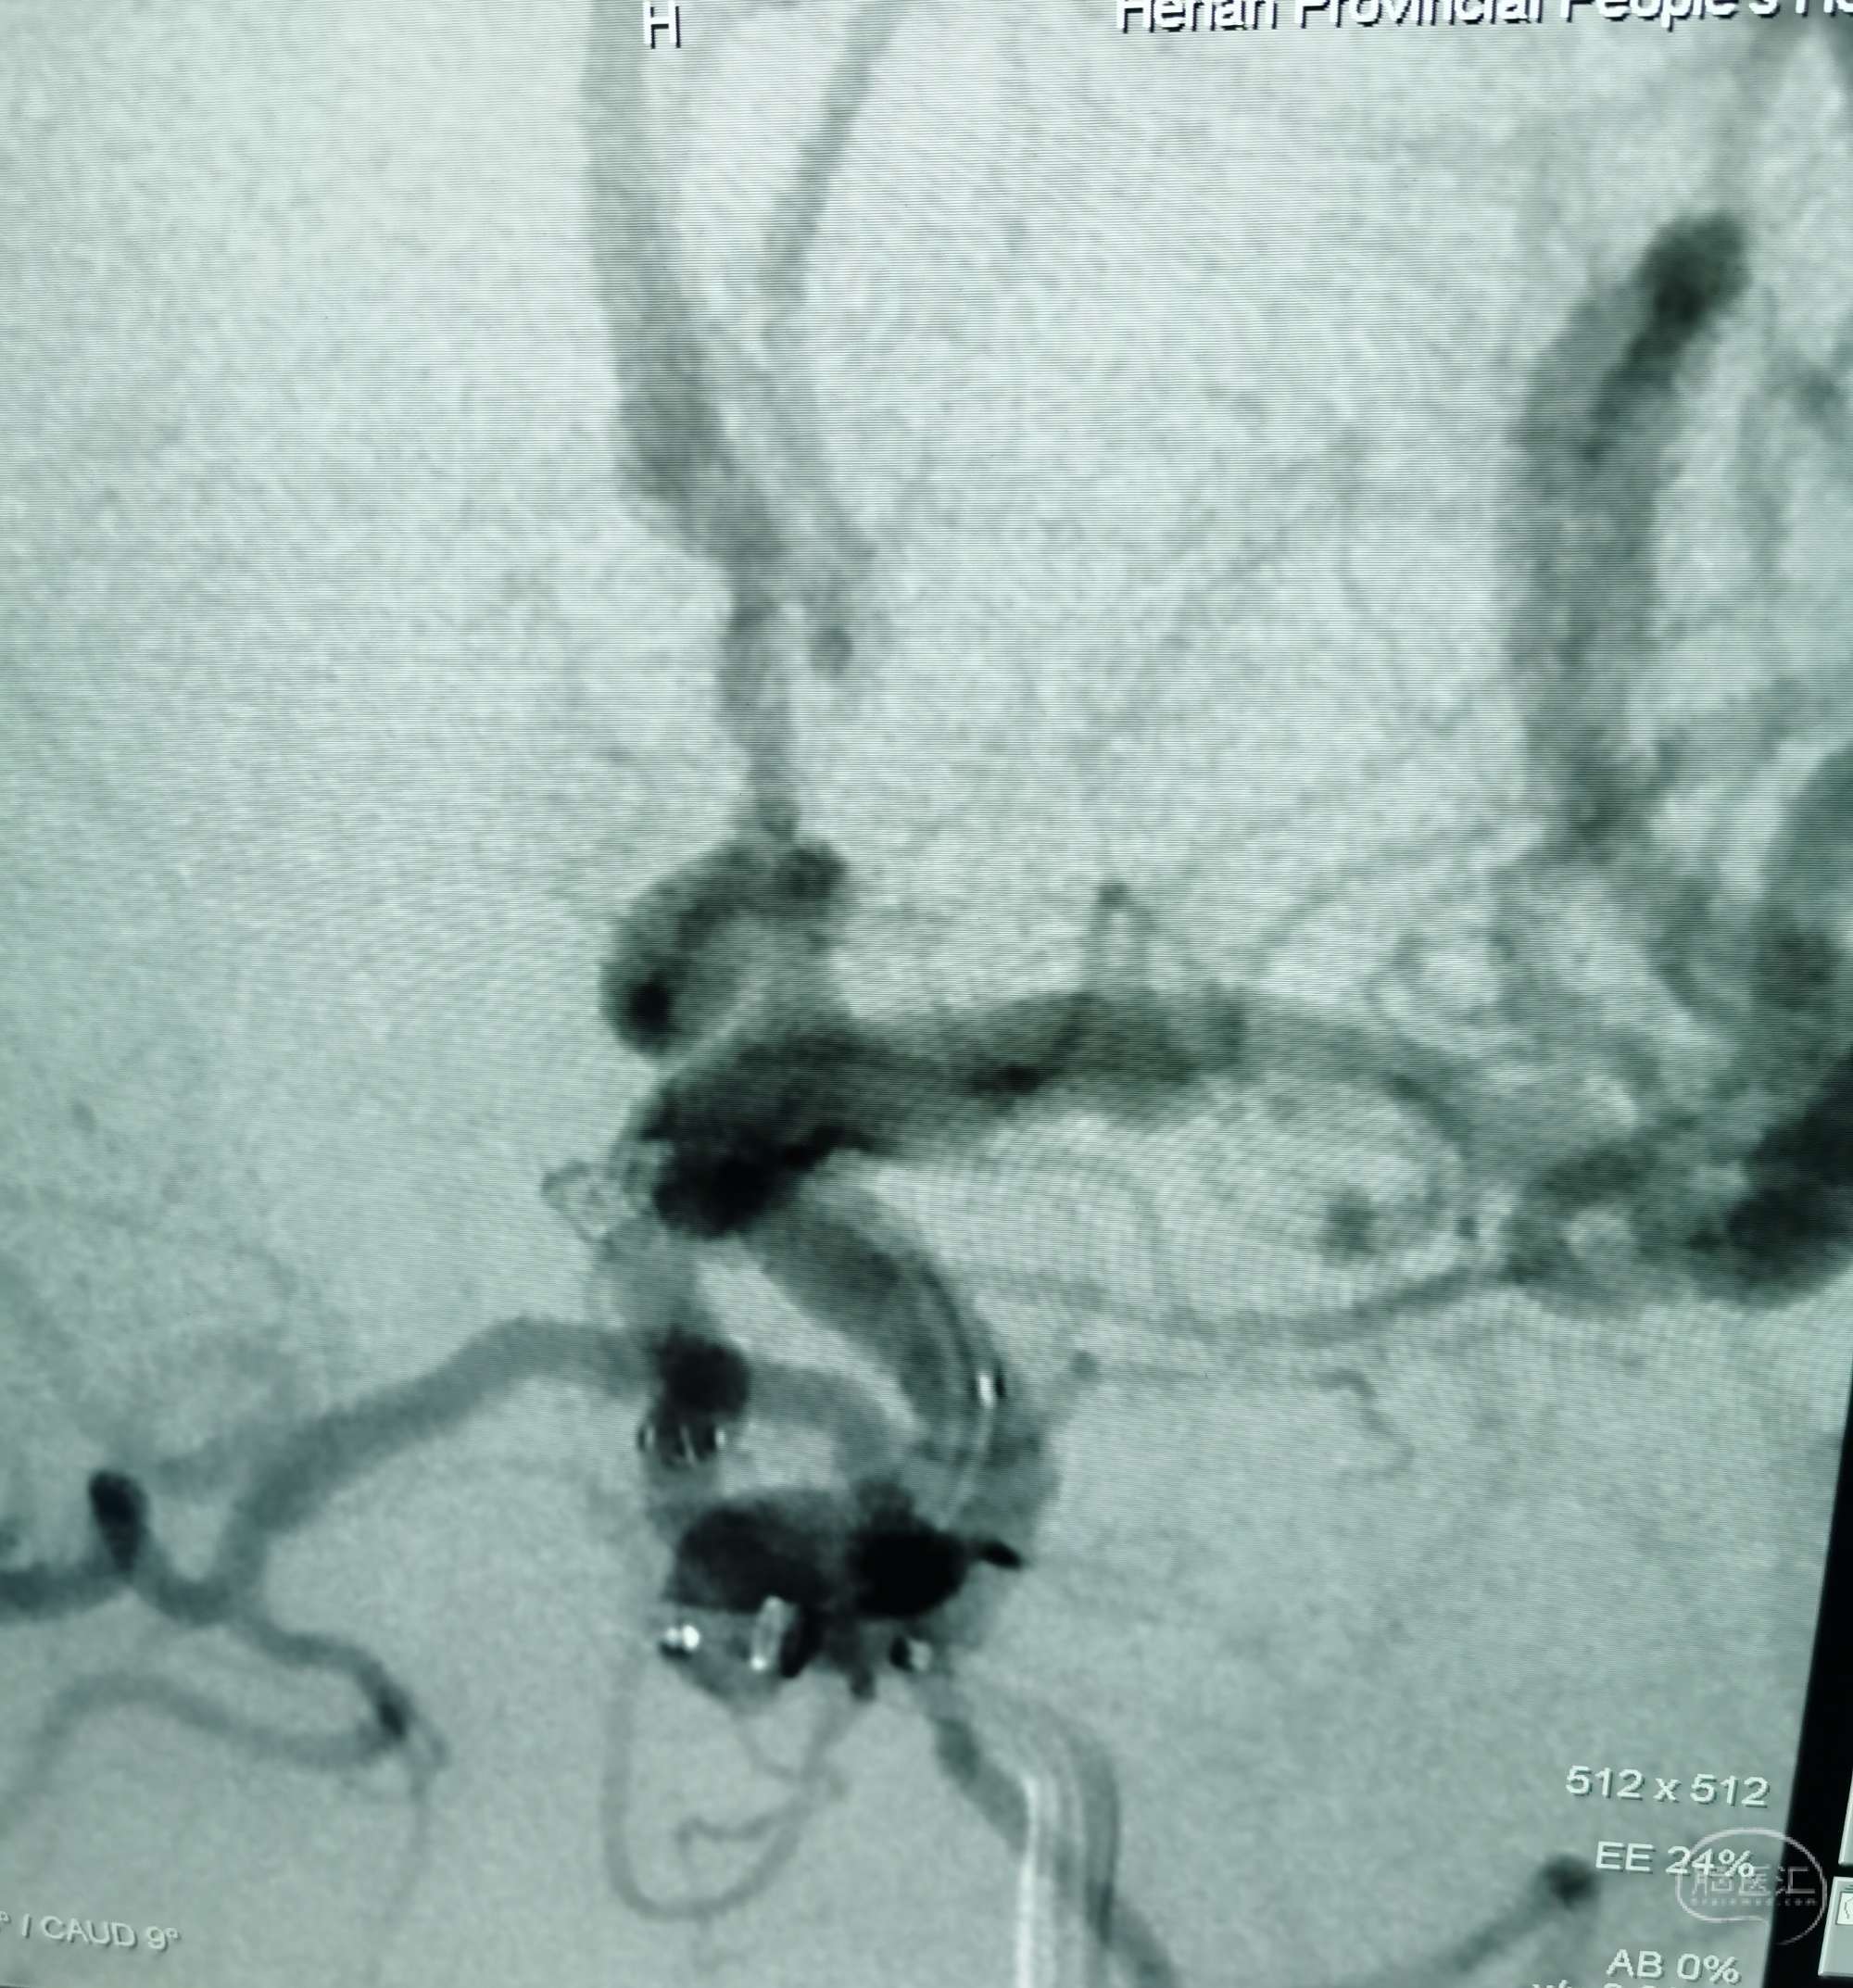

DSA:右侧大脑中动脉、大脑前动脉闭塞,烟雾样血管形成。

颞浅动脉未向颅内代偿。

行颞浅动脉-M4端侧吻合。

吻合14针。

荧光造影示:吻合桥动脉通畅。